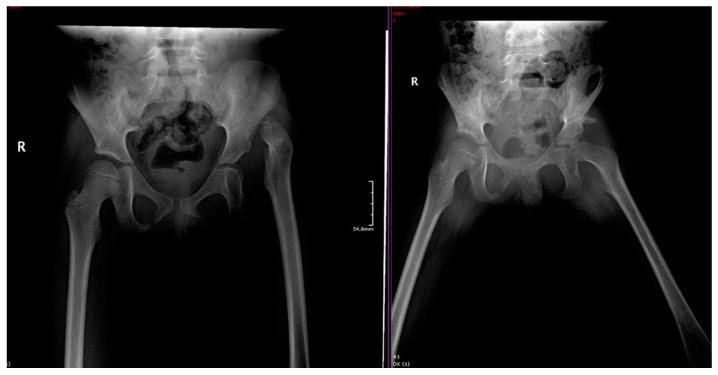

In adults, developmental dysplasia of the hip (DDH) represents a spectrum of disorders. It is commonly found in women in routine orthopedic practice. Hip dysplasia is a leading precursor of joint laxity; when untreated, it can contribute to chronic modifications, such as thickening of the pulvinar and ligamentum teres (which can also elongate), hypertrophy of the transverse acetabular ligament, and osteoarthritis. DDH is presumed to be associated with alterations in pelvic morphology that may affect vaginal birth by the reduction in the transverse diameter of the pelvic inlet or outlet. Here, we provide an overview of the current knowledge of pregnancy-associated DDH. We primarily focused on how a surgical DDH treatment might influence the pelvic shape and size and the effects on the mechanism of birth. We presented the female pelvis from the standpoint of bone and ligament morphology relative to a pelvic osteotomy. Then, we described whether the pregnancy was impacted by previous surgical DDH treatments, performed from infancy to adulthood. In conclusion, hip dysplasia is not associated with high-risk complications during pregnancy or with increased difficulty in vaginal delivery.

在成年人中,发育性髋关节发育不良(DDH)代表了一系列疾病。在常规矫形实践中,女性中常见。髋关节发育不良是关节松弛的主要前驱病变;如果不治疗,它可能导致慢性改变,如 Pulvinar 和teres 韧带(也可能延长)增厚、横髋臼韧带肥大和骨关节炎。DDH 被认为与骨盆形态的改变有关,这些改变可能会通过减少骨盆入口或出口的横径来影响阴道分娩。在这里,我们提供了与妊娠相关的 DDH 的最新知识概述。我们主要关注的是手术治疗 DDH 如何影响骨盆的形状和大小,以及对分娩机制的影响。我们从与骨盆切开术相关的骨骼和韧带形态的角度描述了女性骨盆。然后,我们描述了先前从婴儿期到成年期进行的手术 DDH 治疗是否会影响妊娠。总之,髋关节发育不良与妊娠期间的高风险并发症或阴道分娩难度增加无关。